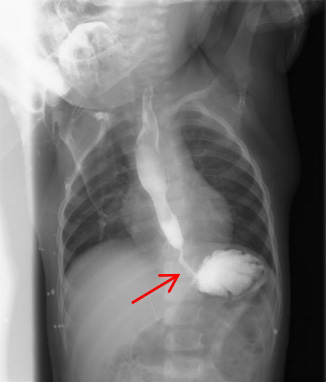

①上消化道造影:为首选检查,可以了解狭窄的部位、程度及范围(如图1)。

图1:先天性食管狭窄患儿的消化道造影检查。红色箭头:食管狭窄段。